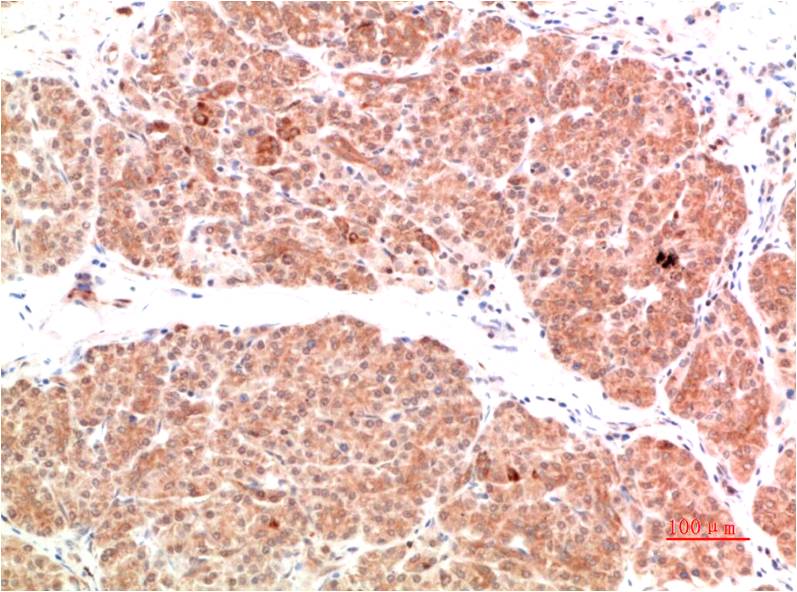

Product name: PI3 Kinase P85 Rabbit pAb

Dilutions: IHC 1:200-500

Background: Phosphatidylinositol-4,5-bisphosphate 3-kinase (also called phosphatidylinositide 3-kinases, phosphatidylinositol-3-kinases, PI 3-kinases, PI(3)Ks, PI-3Ks or by the HUGO official stem symbol for the gene family, PI3K(s)) are a family of enzymes involved in cellular functions such as cell growth, proliferation, differentiation, motility, survival and intracellular trafficking, which in turn are involved in cancer.